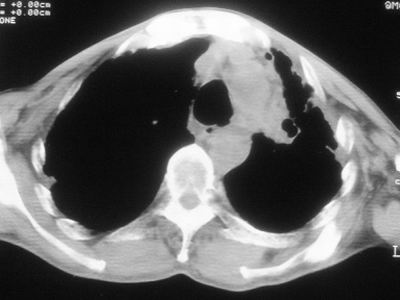

标题: CT11864:男,47岁,反复咳嗽、咯痰、咯血3年,请分析. [打印本页]

患者,男,47岁,反复咳嗽、咯痰、咯血3年,再发5天。痰培养未找到真菌、抗酸杆菌、癌细胞。

左肺上叶体积明显缩小,其内见多发透光区,纵隔向左侧移位,左肺下叶多发班片状病灶,边界模糊,1左肺上叶先天肺发育不全,2左肺下叶肺炎,

左肺上叶结核伴肺纤维化,纵隔移位,左肺下叶感染性病变,建议抗炎抗结核后复查,双肺气肿.

考虑:左肺慢纤伴霉菌球形成、双肺全小叶型肺气肿。

1)考虑为:左肺上叶肺结核(空洞形成),伴左下肺感染;不排除霉菌感染可能。2)肺气肿。

左肺上叶结核伴肺纤维化空洞形成并左肺下叶感染,纵隔牵拉移位,建议作进一步检查排除左侧肺霉菌感染可能。